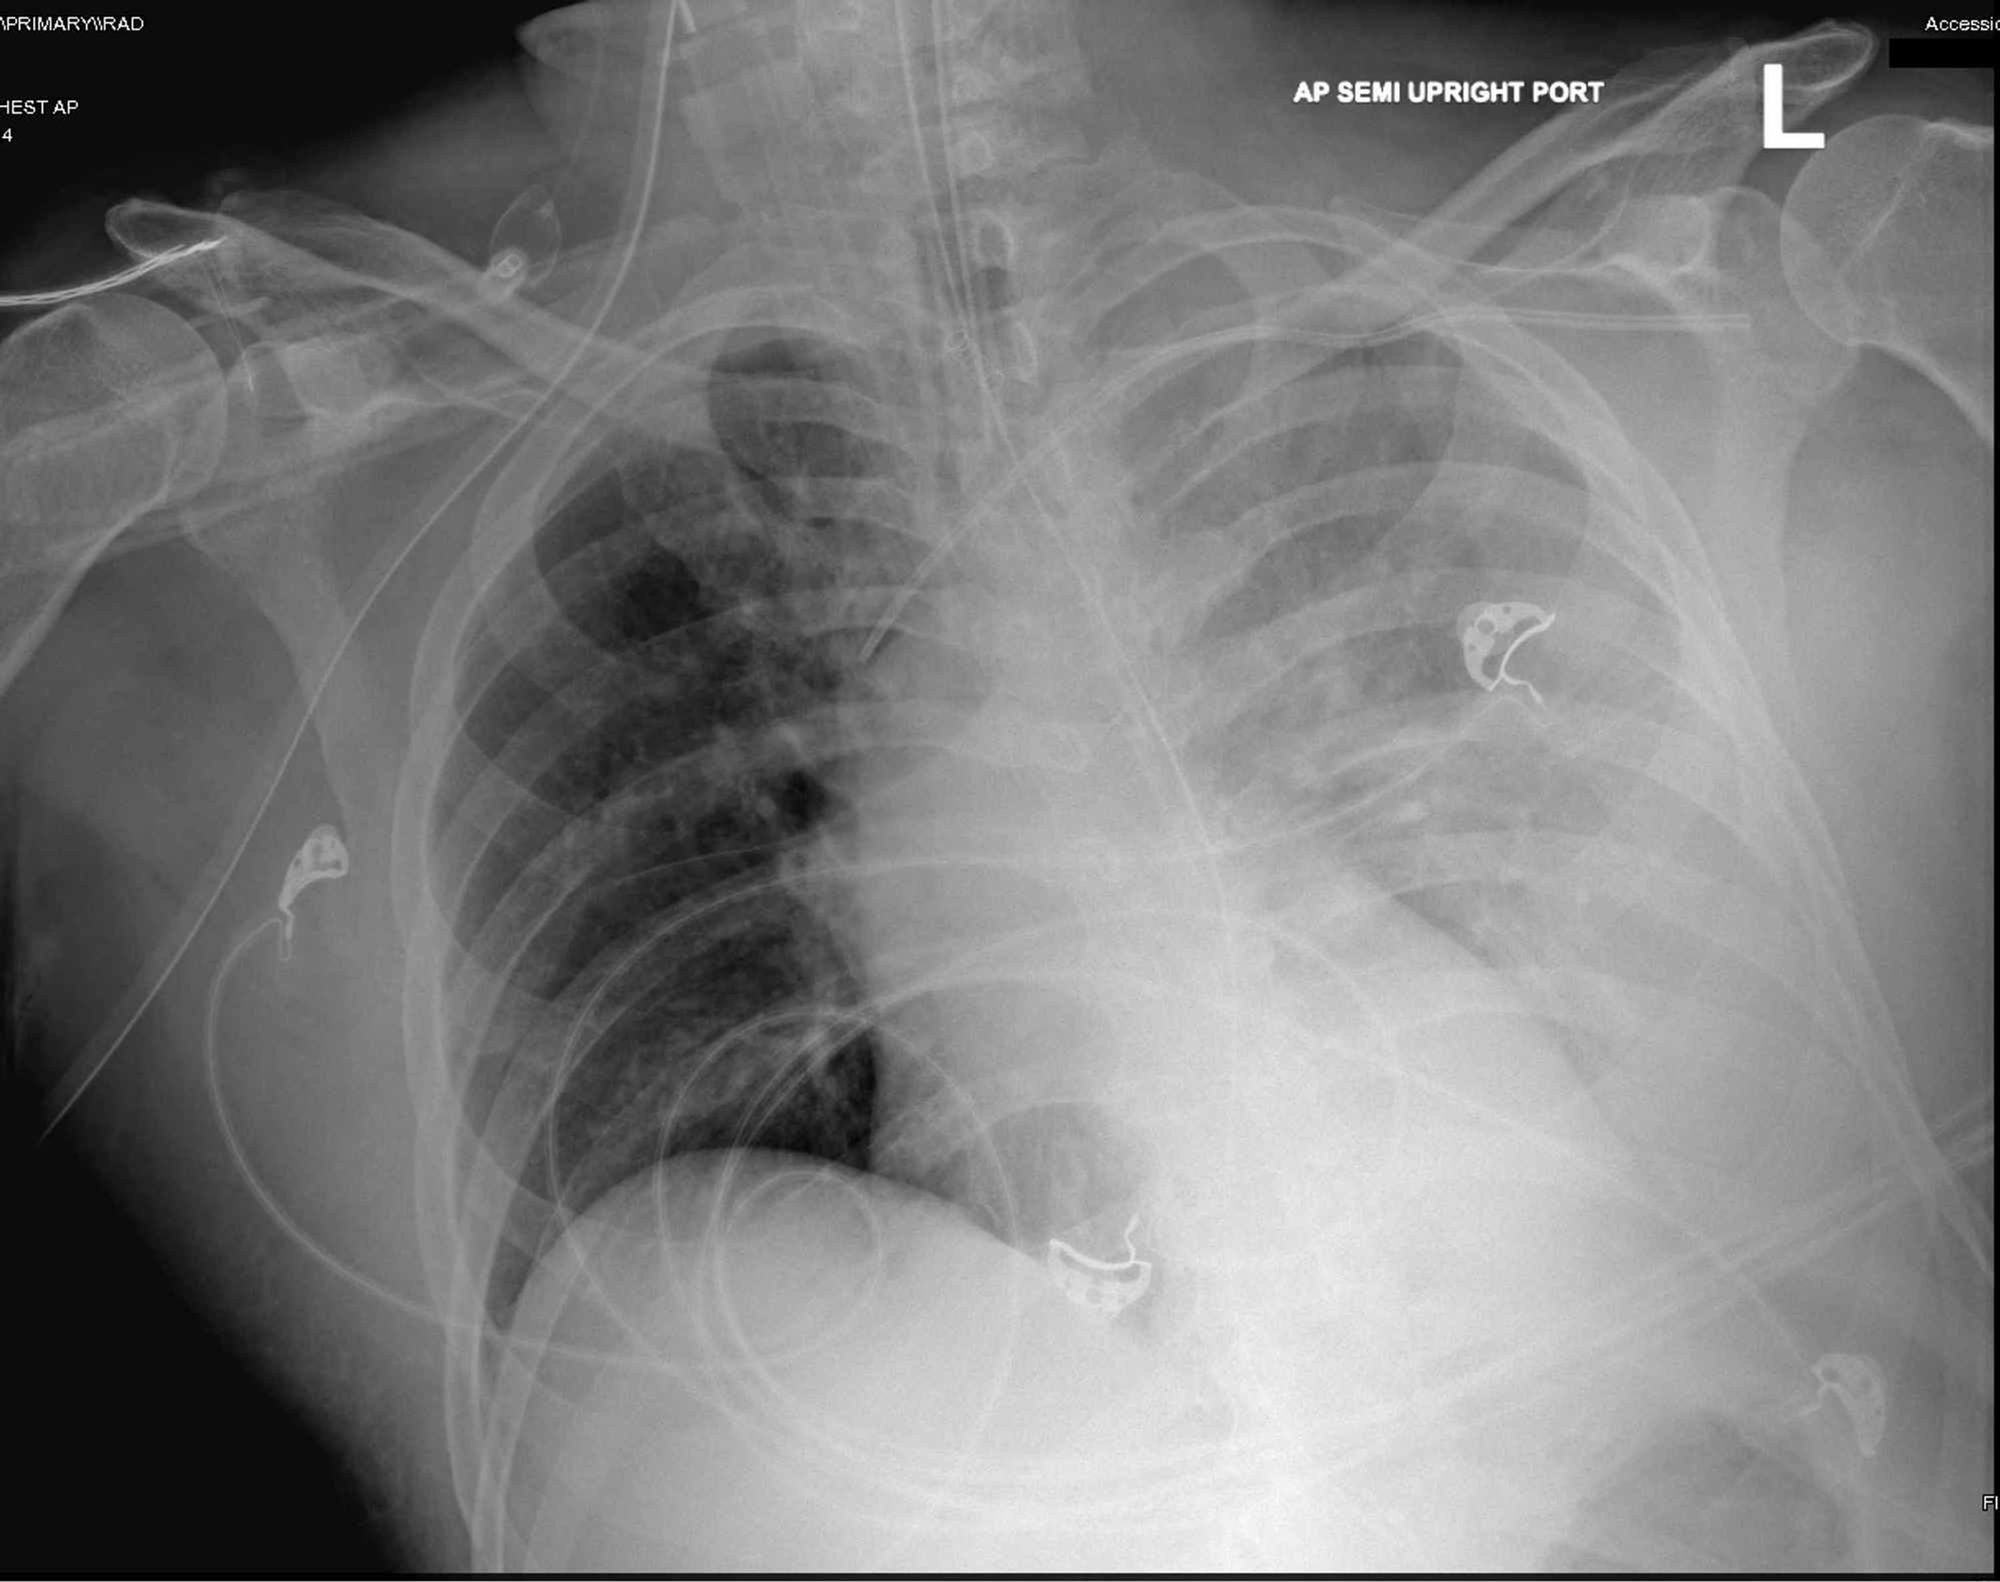

Severe Sepsis Lungs . Severe sepsis or septic shock is characterized by an excessive inflammatory response to infectious pathogens. Sepsis causes an inflammatory response in your body. Severe sepsis occurs when one or more. Severe sepsis was defined as the progression of sepsis to organ dysfunction, tissue hypoperfusion, or hypotension. Septic shock was described as hypotension and. Sepsis is a serious condition in which the body responds improperly to an infection. Sepsis is the main indirect cause of ards in the icu (35), and the lungs are the first and most vulnerable organ affected by sepsis.

Sepsis is the main indirect cause of ards in the icu (35), and the lungs are the first and most vulnerable organ affected by sepsis. Sepsis is a serious condition in which the body responds improperly to an infection. Severe sepsis occurs when one or more. Severe sepsis or septic shock is characterized by an excessive inflammatory response to infectious pathogens. Severe sepsis was defined as the progression of sepsis to organ dysfunction, tissue hypoperfusion, or hypotension. Sepsis causes an inflammatory response in your body. Septic shock was described as hypotension and.